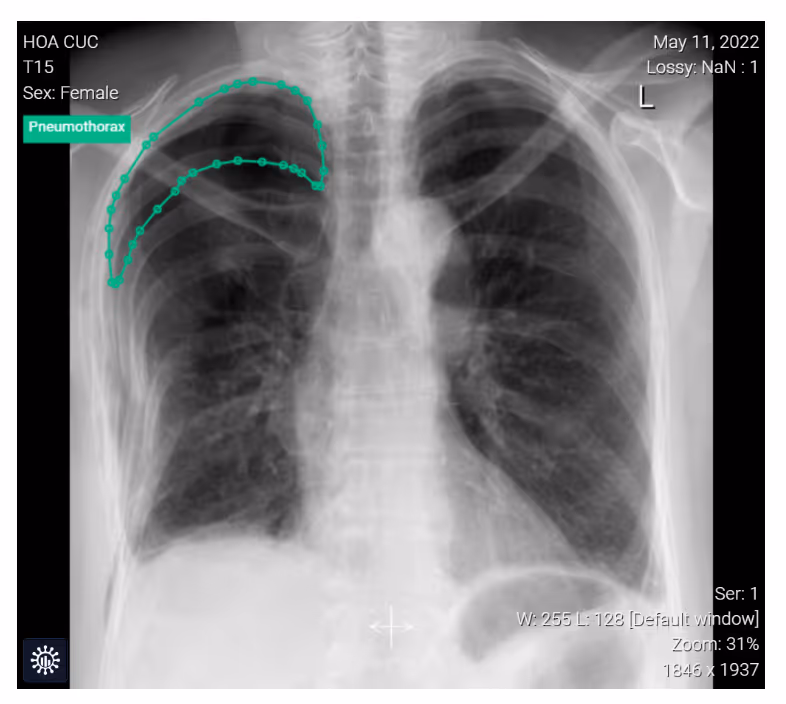

- A 55-year-old female toppled to the right side experiencing thoracic tenderness and mild shortness of breath.

- Image findings:

- Partially displaced rib fractures and a pneumothorax on the right side.

- Fractures of the right ribs 3-8 were obvious with a displacement of the 5th and 6th ribs.

- The thin pleural line and the lack of the pulmonary vessels in the right apex visibly reflect a pneumothorax.

- Subcutaneous emphysema of the thoracic wall.